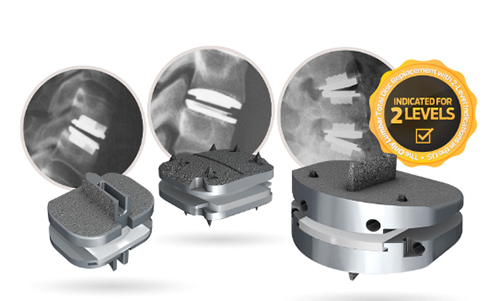

The prodisc L implant has been designed to maintain the physiological range of motion in the spine. The implant was developed using the clinically proven ball and socket concept used in joint replacement implants for over 40 years. The prodisc L implant is composed of three components – two cobalt chrome alloy (CoCrMo) endplates and an ultra-high molecular weight polyethylene (UHMWPE) inlay.

Secure Fixation

- Patented central keel and lateral spikes provide secure primary fixation

- Plasma-sprayed titanium surface on bone contacting surfaces promotes integration

Anatomical Sizing

12 anatomical combinations facilitate an accurate match with the patient’s anatomy

- Medium and large footprints

- 10, 12 and 14 mm heights

- 6° and 11º lordotic angles